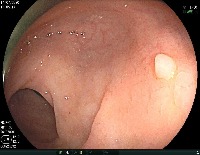

Hyper_Kvasir dataset segmented image part, annotated in YOLO format. Suitable to train object detection models. if you use this dataset than cite the orignal paper of this dataset